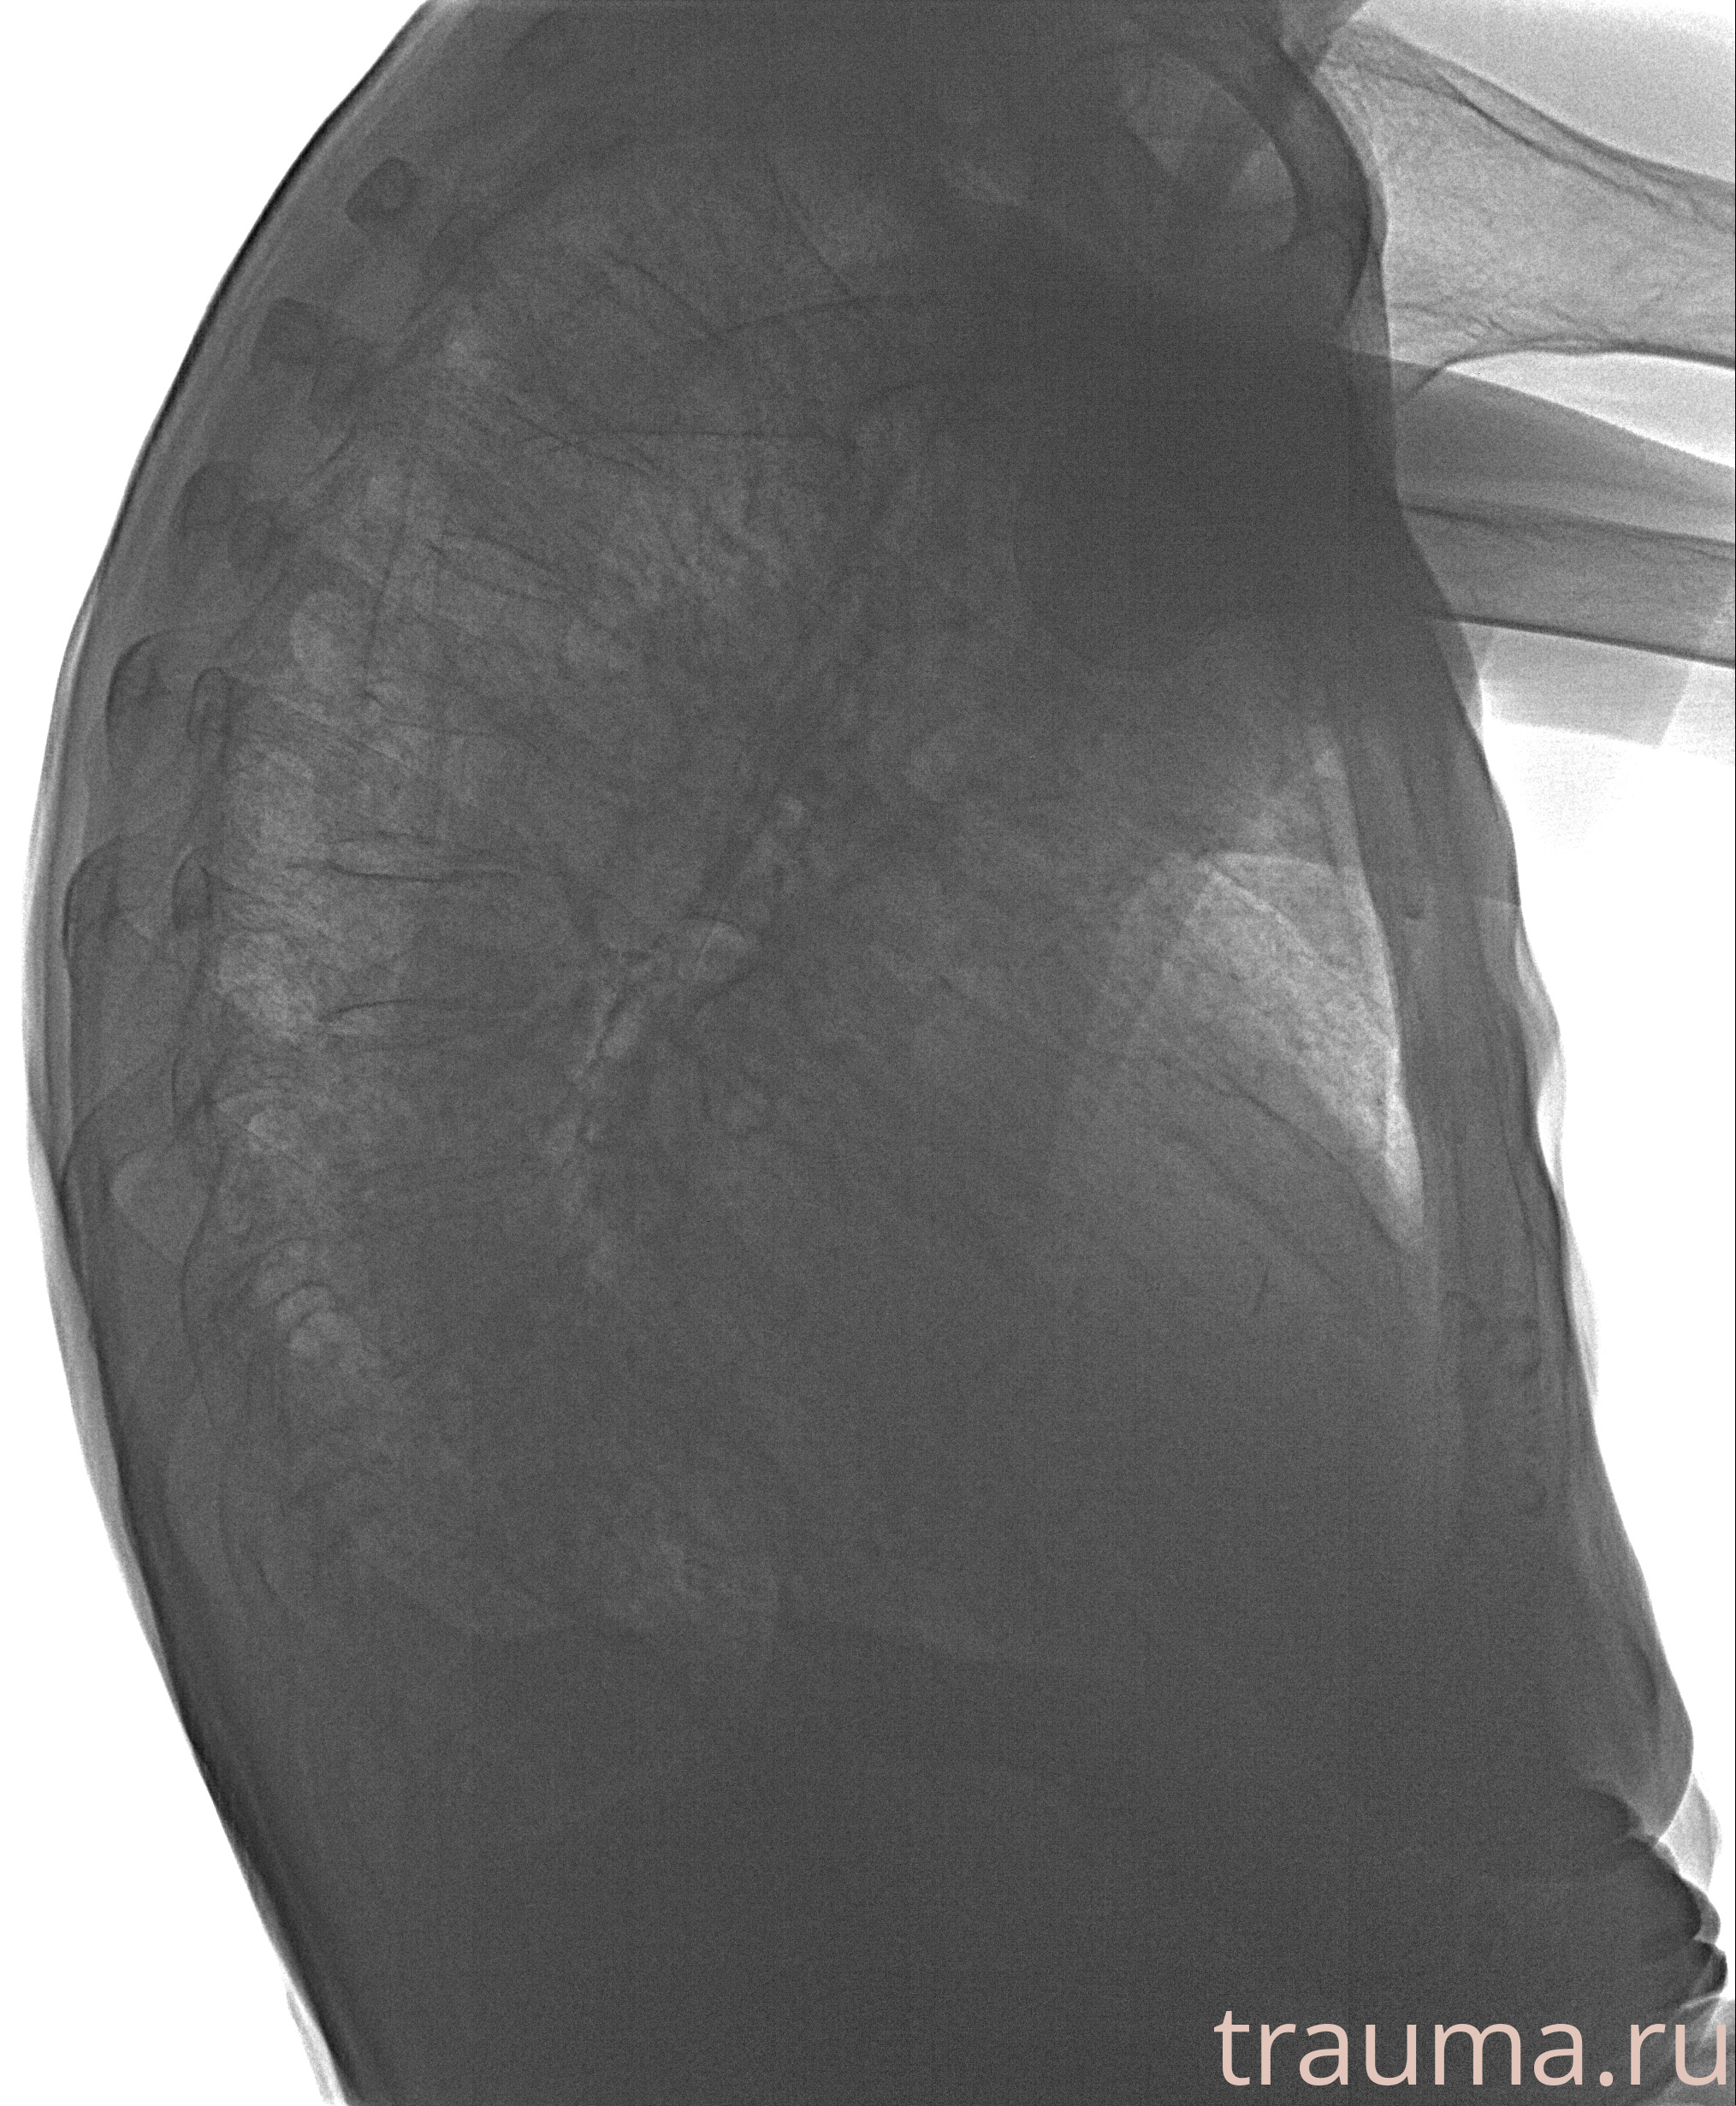

Рентген на дому: по вашему адресу приезжает врач-рентгенолог, травматолог-ортопед с мобильным рентгеновским аппаратом, проводит диагностику травмы или заболевания, делает необходимые рентгенограммы, дает рекомендации по дальнейшему лечению. Получить качественные снимки в домашних условиях возможно благодаря уникальной методике, разработанной МосРентген Центром для института  Склифосовского